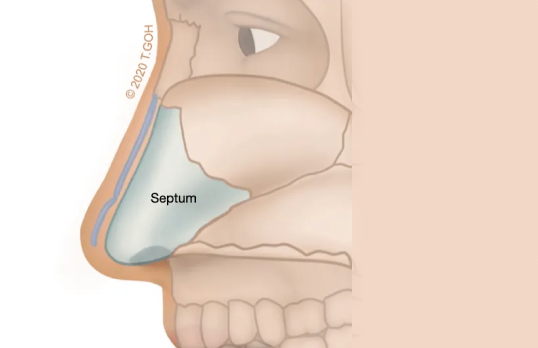

Although not visible, the septum is a necessary support structure for the nose and serves as the foundation for the tip. Patients with a weak or poorly formed septum may require septal extension grafts to establish a stable base. Without this reinforcement, the tip may droop or lose height over time.